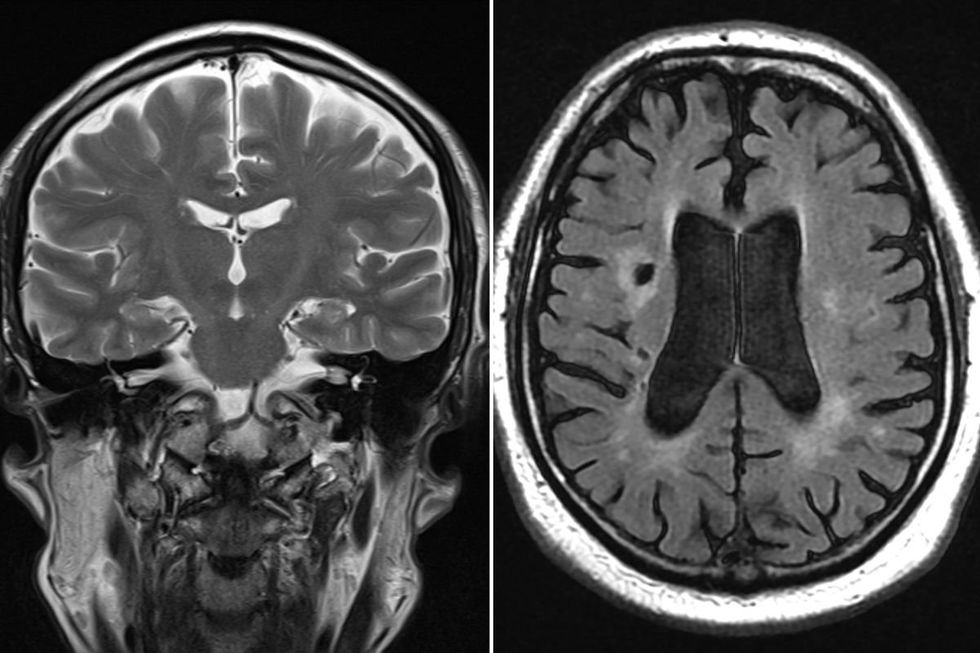

The body needs seven to nine hours of quality sleep nightly for optimal cardiovascular wellbeing

|GETTY

"When we go to sleep, we go into physiological processes that actually help us regenerate some of our tissues, brain neurotransmitters; we kind of reset ourselves," she said.

"Every single biological cell and tissue in the body depends on sleep to be able to maintain itself during wakefulness."

Prolonged sleep deprivation can elevate stress hormones such as cortisol, potentially contributing to cardiac disease development.

The American Heart Association advises adults to obtain seven to nine hours of quality sleep nightly for optimal cardiovascular wellbeing.